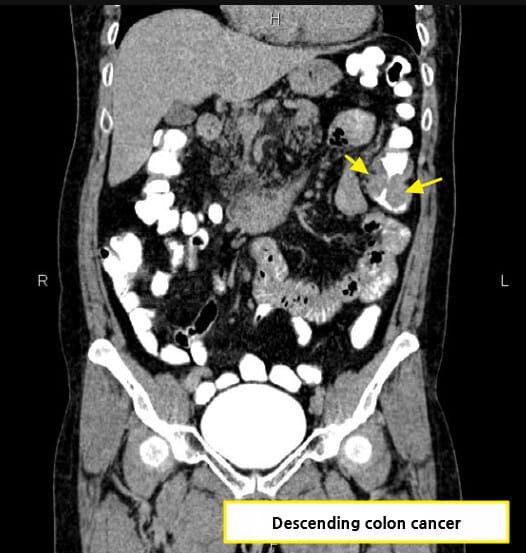

CT 소견 (Contrast-enhanced CT)

🔵 장벽 비후 (Bowel wall thickening)

암 부위의 장벽이 국소적으로 두꺼워지며, 조영증강되는 불균일한 덩어리로 관찰됩니다.

🔵 Annular constricting mass

암이 장을 원형으로 둘러싸며 협착을 유발하는 고전적 폐색 패턴입니다.

Niknejad M, Colon cancer. Case study, Radiopaedia.org (Accessed on 15 Jul 2025) https://doi.org/10.53347/rID-87193

Abdrabou A, Carcinoma of sigmoid colon. Case study, Radiopaedia.org (Accessed on 15 Jul 2025) https://doi.org/10.53347/rID-23071